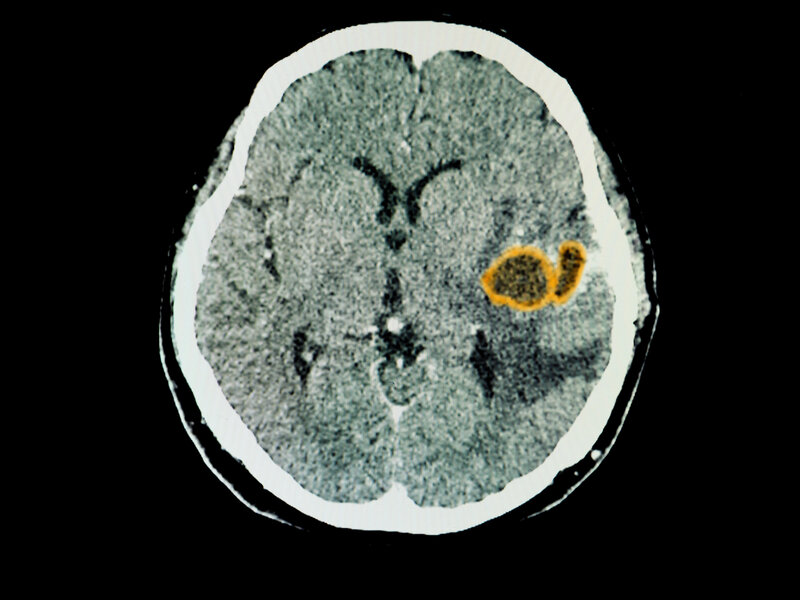

Sind orale Bakterien unterschätzte Verursacher von Hirnabszessen?

Eine Studie der Universität Plymouth und dem University Hospitals Plymouth NHS Trust zeigt, dass orale Bakterien auch dazu beitragen können, dass Patienten potenziell lebensbedrohliche Abszesse im Gehirn entwickeln. Intrazerebrale Abszesse sind zwar relativ selten, gehen aber mit einer hohen Mortalität und Morbidität einher.